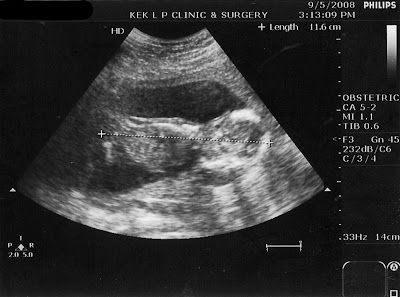

We highly recommend Dr. Kek as we find her calm, composed, confident, very knowledgable and very motherly. Anyway is the 16th week scan. He is about 11.6cm then.